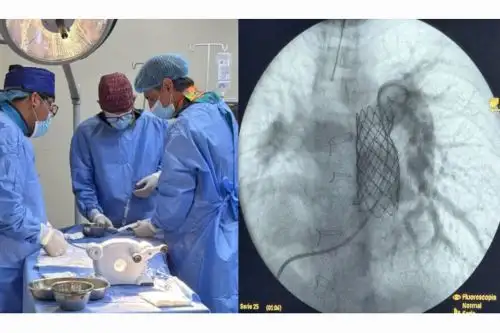

Cardiólogo argentino y equipo de médicos del INSN colocan implante de válvula pulmonar a pacientes con cardiopatía congénita. Foto: Difusión

Un equipo de médicos del Instituto Nacional de Salud del Niño (INSN) junto con el destacado cardiólogo intervencionista de la Fundación Favaloro de Buenos Aires (Argentina), Dr. Germán Augusto Henestrosa, realizaron la colocación de implantes de válvula pulmonar percutáneo, por cateterismo cardiaco, a dos pacientes adolescentes que les permitirá corregir sus problemas en el corazón, sin necesidad de someterlos a una intervención quirúrgica a corazón abierto.

En esta oportunidad, se trata de adolescentes de 14 y 15 años diagnosticados con tetralogía de Fallot, una cardiopatía congénita que involucra cuatro anormalidades: una comunicación interventricular, una obstrucción del tracto de salida del ventrículo derecho, el cabalgamiento de la aorta y la hipertrofia ventricular derecha. Esto puede causar síntomas como falta de aire y fatiga.

Ahora usamos la técnica de colocar una válvula percutánea, y muchas veces en 48 horas el paciente está en su casa. Duran más de diez años sin problemas, y si tuviera que cambiarse, el paciente, ya tendría la estructura o el esqueleto para poner una válvula y el procedimiento de cateterismo sería más sencillo sin acto quirúrgico”, precisó el cardiólogo argentino, quien explicó su experiencia con este tipo de procedimiento.